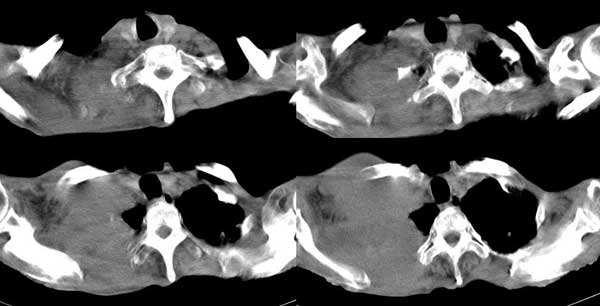

右侧胸廓塌陷。右前上外侧胸壁软组织肿块,其内见有低密度影,肋骨呈溶骨性表现。右肺上叶见大量的间质纤维化表现。右侧膈肌上抬。

肺尖巨大肿块影阴,胸壁受侵肋骨破坏,肿块密度不均且穿破胸壁入皮下,应该是:肺上沟癌;由于肺内有斑片状播散病灶,因此不排除胸壁结核。

我觉得这个人右侧胸部的肿块来源于肋骨或胸壁软组织,从病灶的形态来和最大直径来看,来源于肋骨的可能更大,可以基本定性为恶性。